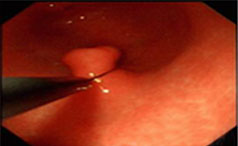

胃息肉患者可能不会有不适症状,也可能会出现消化道症状,在治疗上可选择药物治疗和手术治疗的方式。...【详情】

常见症状:上腹隐痛、腹胀、不适

无痛性便血、脱垂

【导语】一般来说胃息肉的患者没有太多典型的症状表现,但是随着疾病的逐......【详情】